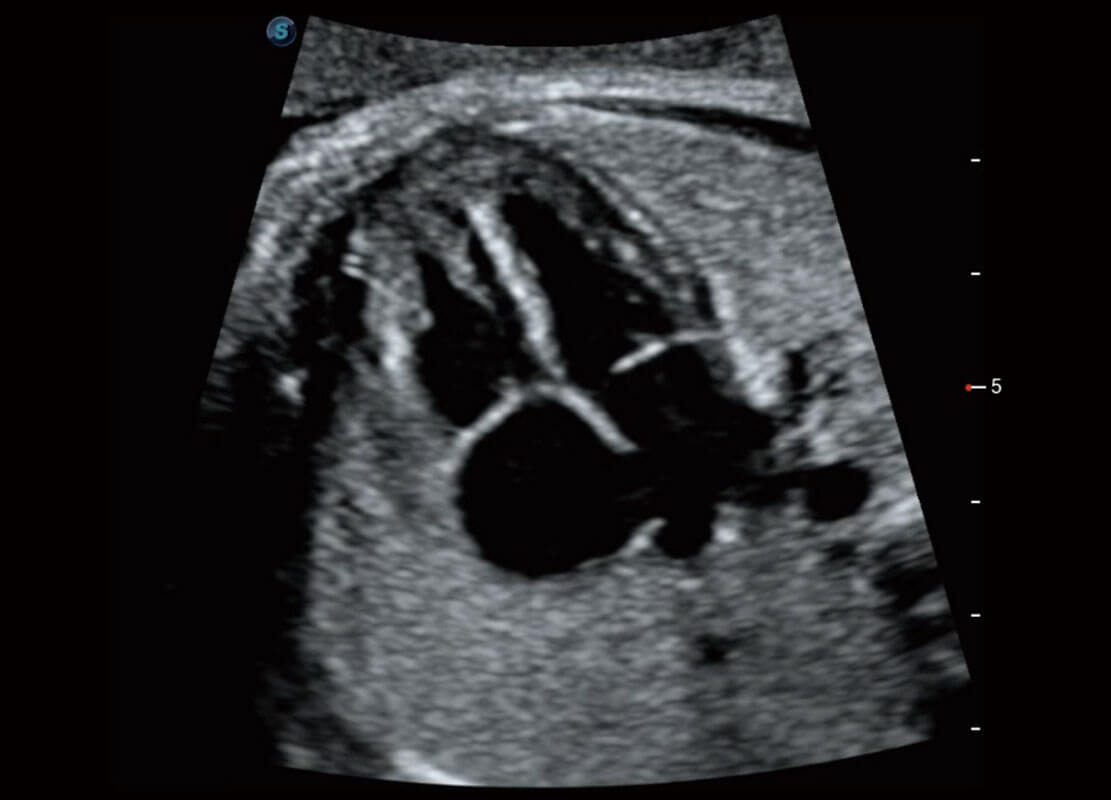

盆底超声

P60为盆底超声检查提供应用方案,多种腔内及腹部容积探头提供从二维、三维到四维的优异图像品质,实时快速三维容积数据获取,专业的测量工具包等人性化设计,为超声医生诊断提供有力保障。

Lev.Hiat A-r: 16.33 cm2

Lev.Hiat H-r: 53.70 mm

Lev.Hiat W-r: 43.96 mm

Lt-LUG-r: 24.16 mm

Rt-LUG-r: 19.94 mm

S-Pelvic

能够简化盆底检查的操作流程,可在二维模式及三维成像模式下实现一键自动提取出标准切面、自动识别当前切面、自动测量,提升盆底检查的高效性,同时也能让青年医生快捷的获得准确的检查结果。